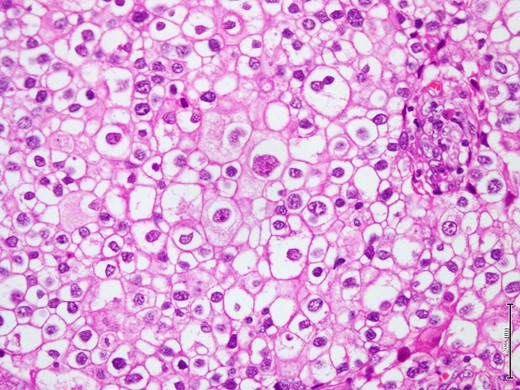

The breast lump was fully excised via a wide local excision along with axillary clearance. The pathological examination of the specimen showed a 3×2.2 cm firmly well circumscribed lesion with unremarkable surrounding fibrofatty tissue. The histological examination showed a Grade 3 invasive clear cell (glycogen rich) carcinoma composed of clear cells with pleomorphic nuclei (Fig. 2). The tumor cells showed intense positivity for Periodic Acid Schiff (PAS), diastase sensitive (Fig. 3A and B), confirming glycogen content in tumor cells. The immunohistochemistry profile showed many cells were positive for Her2 score 3 (Fig. 4), but negative for ER and PR. The only single sentinel lymph node showed tumor metastasis while the other eight retrieved lymph nodes were normal. Neither vascular invasion nor microcalcification noted. The possibility of metastasis was excluded by clinical and radiological investigations. The final pathological stage was pT2 (3 cm in maximum dimension) pN1a (1/9) pM0. The Nottingham prognostic index (NPI) score was 5.6. Post-operative recovery was uneventful.

Shows microscopic appearance of the tumor composed of large polygonal cells with pleomorphic nuclei and well define nuclear membrane (H&E stain, 40X).